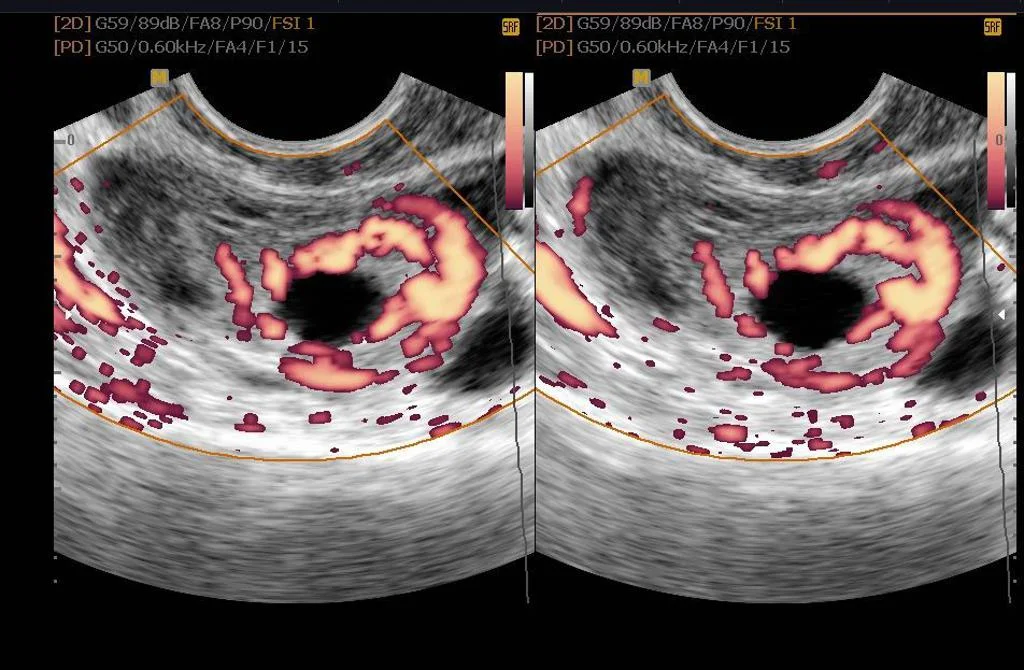

The ring of fire sign also known as ring of vascularity signifies a hypervascular lesion with peripheral vascularity on color or pulsed Doppler examination of the adnexa due to low impedance high diastolic flow 1. This sign can be seen in. Corpus luteum cyst more commonly ectopic pregnancy.

An ill defined heterogeneously echogenic extraovarian oval mass in right adnexa with an eccentrically located cystic structure and peripheral vascularity around it ring of fire sign. The pelvic cavity shows moderate amount of free fluid with floating echoes within suggestive of hemorrhagic fluid. Cindy cindyvamaya has created a short video on TikTok with music 2002.

A corpus luteum of pregnancy will typically show the classic ring of fire pattern which is seen in the first image above in the ovary on the left side of the image. The separate round mass with a ring of hypervascularity demonstrates a classic tubal ring. The ring of fire is something some women experience when their babys head crowns during vaginal birth.

Similarly the ring of fire sign shows peripheral hypervascularity of the hyperechoic ring and represents high-velocity low-impedance flow surrounding the pregnancy. The ring of fire sign however is nonspecific and can be seen around a normal maturing follicle or corpus luteal cyst. Pellerito JS Taylor KJ Quedens-Case C et al.